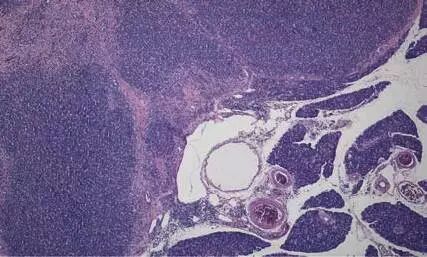

胰腺在多种至关重要的代谢功能中担负着重要的角色。胰腺外分泌部会分泌消化酶,在营养成分的利用过程中必不可少。胰腺外分泌部的炎症和退行性病变在犬猫也十分重要。 本文将概述胰腺外分泌疾病及其诊断方法。 胰腺炎概述 胰腺炎分为急性和慢性。慢性胰腺炎的临床症状可能不明显,而急性胰腺炎则出现十分剧烈的临床症状。只有通过组织学判断组织的损伤程度来鉴别急性与慢性。 为了保护组织器官不被自体消化,消化酶通常以无活性酶原的形式分泌出来。胰腺组织损伤会导致酶释放增多,使胰腺组织和周围脂肪组织受到破坏。 特急性型病例中主要观察到组织坏死,在组织学上(尚)未观察到炎症反应。因此,将这些病例称为急性胰腺坏死更为恰当。 在急性胰腺炎中,主要的炎性细胞为中性粒细胞,并伴有坏死。坏死的胰腺周围脂肪组织呈粗糙的白色颗粒状,并常因包含钙盐而发生钙化。 在慢性胰腺炎中,炎性细胞主要以浆细胞为主。此外,萎缩的胰腺实质会逐渐纤维化,并可能发展为胰腺硬化。 急性胰腺炎/急性胰腺坏死 急性胰腺炎是一种危及生命的综合征,相比犬更多见于猫。 图 1: 猫的急性胰腺坏死(箭头所示),相邻组织宏观表现为正常的胰腺组织(N) 猫的急性胰腺炎通常与(胆管)肝炎和/或肠炎一起发生,而单发型胰腺炎更常见于犬。 该病的病因通常不明,但据推测是由多种因素致病:肥胖、缺乏锻炼和高脂饮食、某些药物 (例如:磺胺类药物、咪唑嘌呤、糖皮质激素)、创伤(例如腹部手术)或全身感染(例如:猫的弓形体病)。 临床症状不具有特异性,并且因不同严重程度而异。典型的症状包括厌食、呕吐、腹泻和腹痛。此外还可能出现发热、呼吸急促,甚至休克。 由于临床症状不典型,就需要特异性间接检测手段以快速有效地进行诊断。至关重要的诊断方法主要是血清学检查(见后文)。 取决于炎症和坏死的严重程度,胰腺功能有可能完全恢复,或胰腺局部坏死时,动物耐过后,坏死部分发生纤维化。 慢性胰腺炎与胰外分泌不全(EPI) 反复发作的急性胰腺炎或无症状的渐进性间质性胰腺炎可发展为慢性胰腺炎。反复发作的急性胰腺炎在犬中较为常见,临床表现为消化不良以及间歇性呕吐和腹泻。这些临床症状通常具有自限性,比急性胰腺炎的病例症状轻微。 化验结果在急性胰腺炎中会发生改变,但是可能会保持在正常范围内。在不发病时,患犬可能不表现出异常,因此许多病例中的消化不良与胰腺炎无关。 如果大部分功能性胰腺组织出现萎缩或被结缔组织取代,病患会由于消化酶分泌不足而表现为胰外分泌不全。临床上,这些动物会发展为慢性腹泻且粪便量变大,出现脂肪痢。这些动物虽然食欲良好,但是体重仍会减轻。 通常用影像学诊断无法观察到胰腺的形态学变化,因此需要借助间接检查手段来确诊“胰外分泌不全”。 结节性增生 胰腺外分泌部的结节性增生在老龄犬猫较为常见。 临床上,这样的结节性增生没有临床相关性,通常都是在开腹手术过程中偶然发现的。结节性增生通常表现为多个散在于胰腺实质中的小结节。组织学上,这些结节内由无包膜的部分增生组织混合部分正常腺泡构成。 在猫的病例中,需要与猫胰岛淀粉样变性进行鉴别诊断。 胰腺外分泌部肿瘤 犬猫胰腺外分泌部的肿瘤较为罕见。 (良性)胰腺腺瘤极其罕见,而且就算通过组织学检查,也很难与结节性增生进行区分,几乎没有临床意义。 通常胰腺癌可起源于外分泌导管或腺泡。人常见导管起源的癌,而犬猫则更常见腺泡起源的癌。其表现为胰腺内单个或多个肿物,呈浸润性生长并且表现出早期转移倾向(尤其是转移至肝脏、淋巴结、肠道、肺脏和腹膜),因此在诊断出这类肿瘤时通常已经发生转移。 图 2: 猫 分化良好的胰腺癌 胰腺疾病的诊断 血清脂肪酶和血清淀粉酶 在胰腺炎和胰腺坏死病患体内,这两种酶的血清水平会升高。但是只有当化验结果超过正常值上限的三倍时才有诊断意义。 假阳性和假阴性结果都常见,尤其是猫,因为在其他系统病变时(例如:肝病、肾衰)血清脂肪酶和淀粉酶水平也会升高,反之,也可能忽略明显的血清水平升高。 胰脂肪酶 (cPLI, fPLI) 检测胰脂肪酶免疫反应的特异性很高,敏感性尤其高。PLI具有种属特异性,并且只分布于胰腺。 直到近年来,由于只能在美国一家拥有专利的实验室进行检测,PLI检测仍旧十分困难。 LABOKLIN实验室2013年建立了一种能够与美国PLI检测媲美的PLI检测方法。因此,能够更快获得PLI的检测结果,并且不需要额外费用。 胰蛋白酶样免疫反应 (cTLI, fTLI) 应认为cTLI或fTLI是评估胰腺功能不全的最重要指标。这种检测会同时检测血清中胰蛋白酶和胰蛋白酶原的含量。 在EPI的病例中,上述指标数值会显著下降。 此外,TLI值的明显上升可提示胰腺炎。但是判读结果的关键在于动物在采血前已经禁食。TLI值在肾衰病例中也可显著升高,特别是猫,因此也应考虑肾脏指标。 检测项目说明 检测项目代号及名称:3003 TLI-test 送检样本:血清0.5ml 报告周期:7-9个工作日 胰腺活检-组织学检查 显然,通过手术采集胰腺的活检样本更加困难。如果送检样本包含典型的病变区域,则能够判断胰腺损伤的类型和严重程度。 由于急性胰腺炎病患的麻醉风险会升高,组织病理学在这类病例中发挥的作用是有限的。但是,如果为了诊断不明病因的肠道问题而进行开腹探查,则应该采集全层胃壁样本、肠道样本、淋巴结样本和肝脏样本,并采集胰腺样本,以对全面了解病情及诊断慢性病变。 但是,组织病理学在诊断胰腺肿瘤时十分必要。 结论 在临床上,由于大多数患病动物没有特异性临床表现,胰腺外分泌部疾病的诊断是一项重大挑战。血清学检查至关重要,必要时还应进行活检。 表: 胰腺外分泌部实验室检测指标—参考值 脂肪酶 淀粉酶 TLI PLI 正常值 犬: < 300 犬:< 1650 犬: 5 -50 犬: < 200 胰腺炎 多变 通常升高 多变 通常升高 犬: > 50 犬: > 400 胰腺功能不全 多变 多变 犬: < 2.5 多变